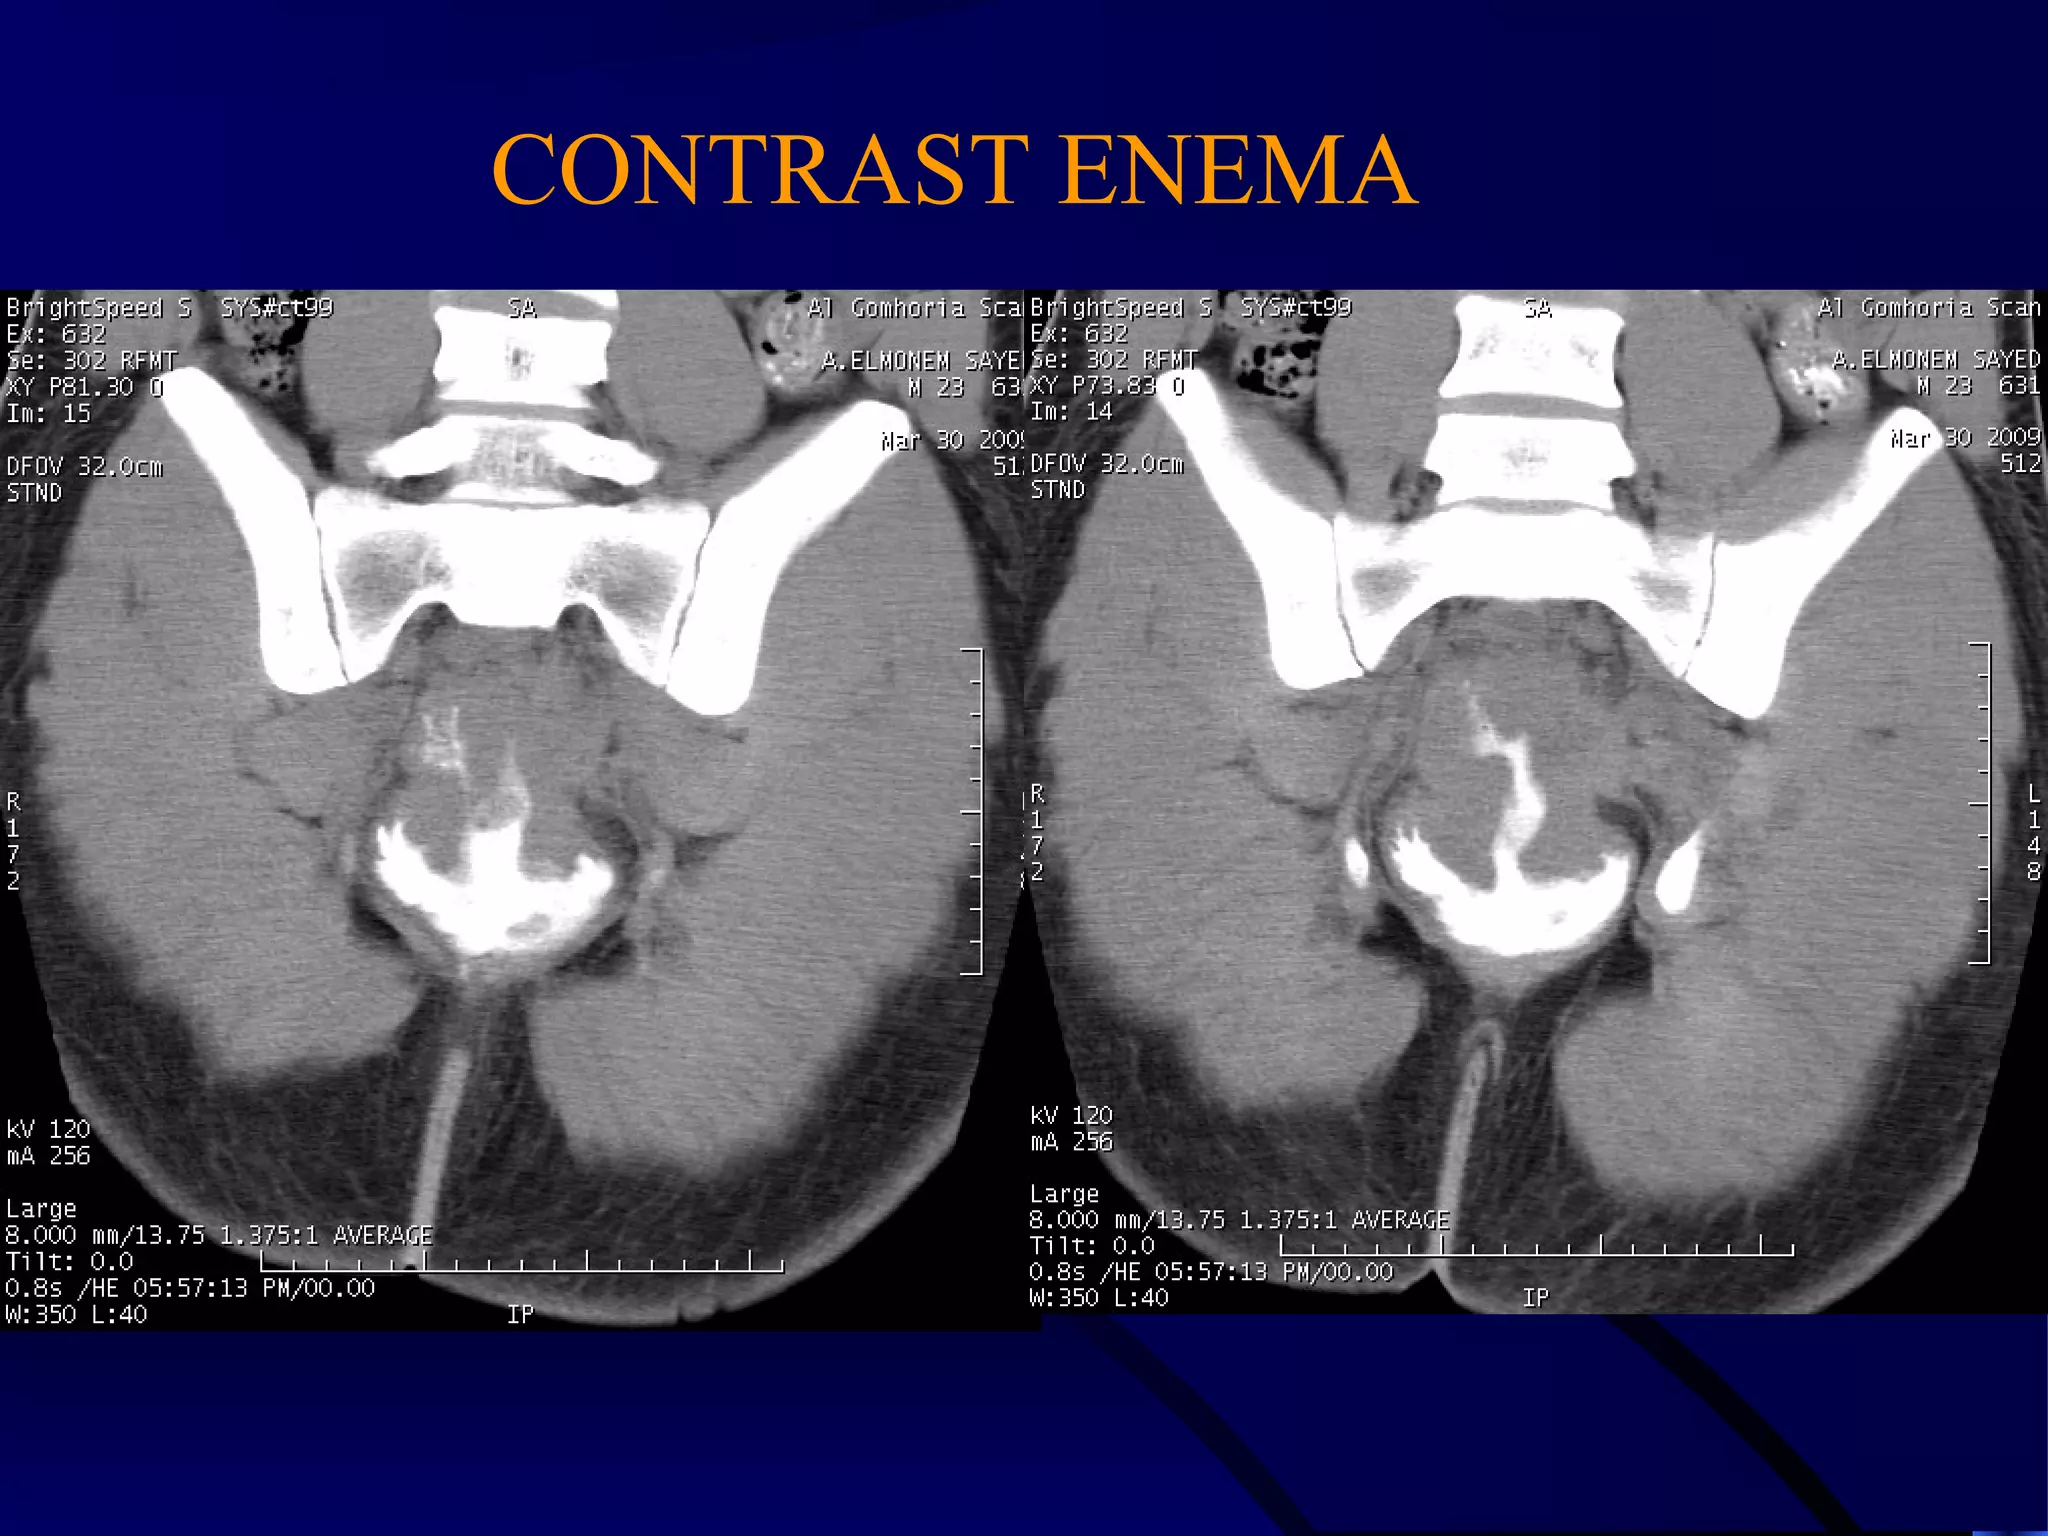

CONTRAST ENEMA